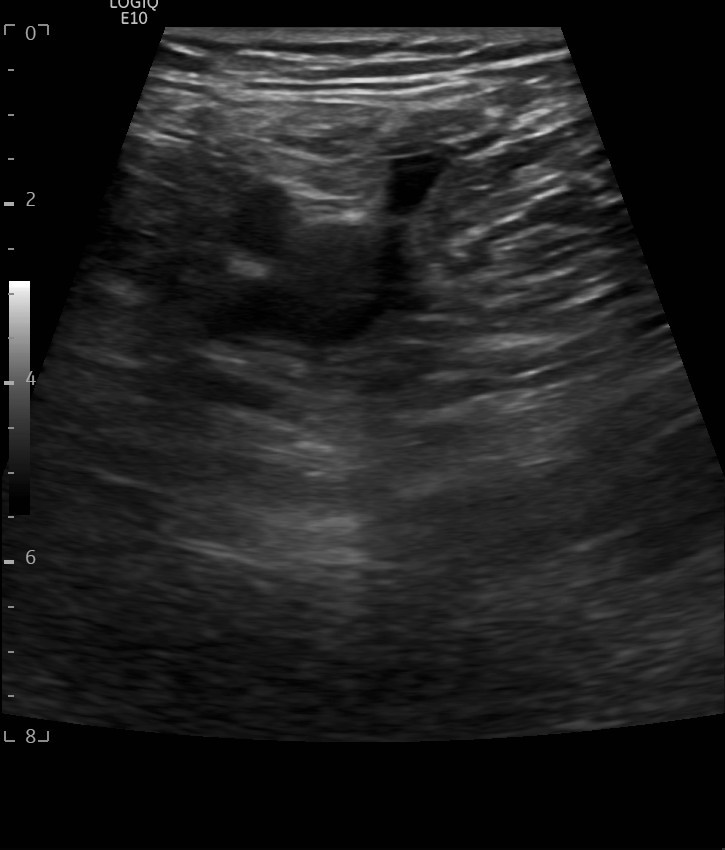

Hallazgos ecográficos

Hallazgos ecográficos: se realiza una ecografía del sistema venoso profundo en 2 puntos demostrando la completa compresibilidad del mismo, no presencia de material ecogénico y buenos flujos en el Doppler color, descartándose trombosis venosa profunda (TVP).

Se realiza una ecografía cutánea: se observan imágenes de “patrón en empedrado o adoquinado”, sugestivo de posible celulitis.